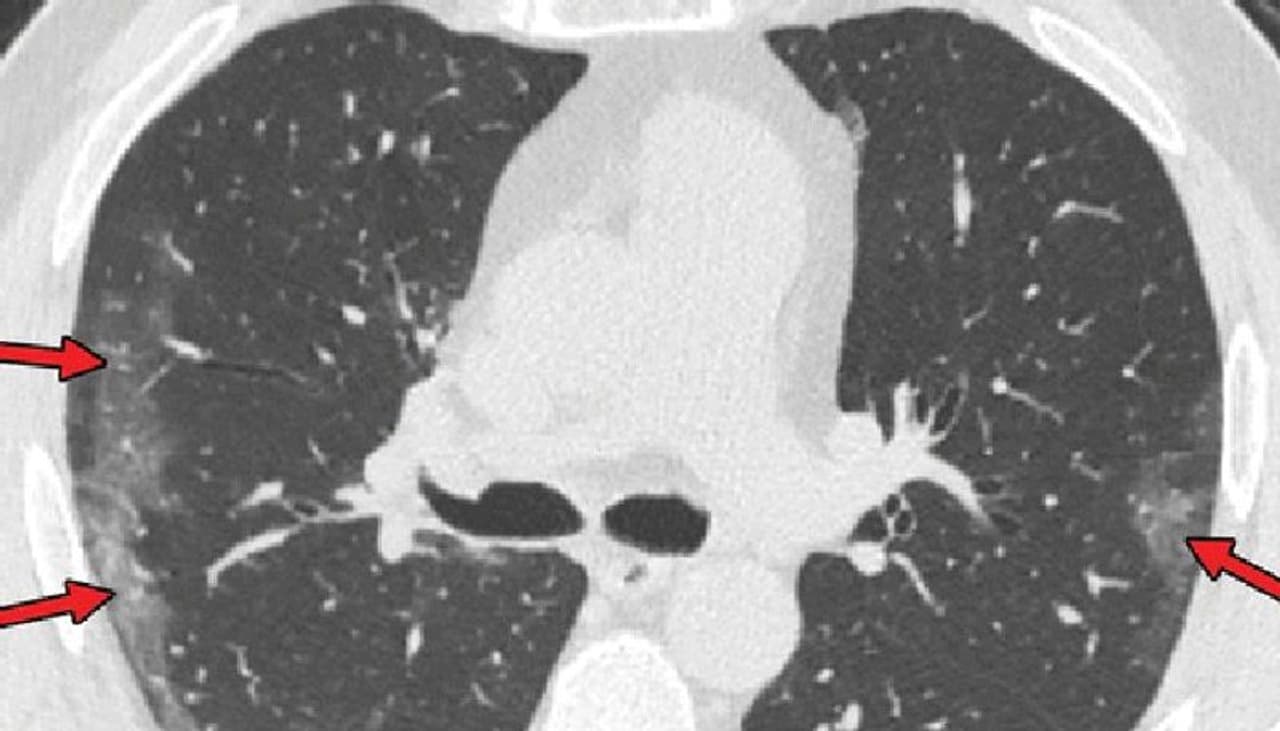

പലയിടങ്ങളിലും രോഗികള് ടെസ്റ്റ് ഫലം 'നെഗറ്റീവ്' ആയി കാണിച്ചതോടെ പോവുകയും പിന്നീട് ലക്ഷണങ്ങള് മൂലം തിരിച്ച് ആശുപത്രിയിലെത്തുകയും ചെയ്യുന്നതായും റിപ്പോര്ട്ടുകളുണ്ട്. ഇവരില് തന്നെ പിന്നീട് എച്ച്ആര്സിടി (സ്കാന്), ബ്രോങ്കോസ്കോപ്പി തുടങ്ങിയ പരിശോധനകളിലൂടെ കൊവിഡ് വൈറസ് സാന്നിധ്യം കണ്ടെത്തപ്പെട്ടതായും വാര്ത്തകള് പുറത്തുവരുന്നുണ്ട്.